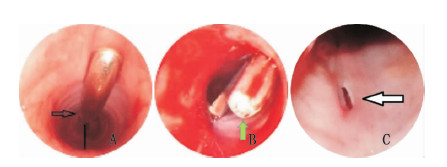

每组均有2只小型猪出现了术中的轻度出血。ST组另有3只发生了术中中度出血,3只由于较长时间缺氧出现了低血压,1只有术后的轻度出血,并可能由此导致了创口感染。SC组1只有术中中度出血,1只有轻度喉部软骨损伤,并导致拔管困难,但根据术后2个月的气管镜检查,并未见明显的气管狭窄,推测拔管困难的原因是环甲膜创口周围的肉芽增生。通过纤维支气管镜可见CMPGT组的穿刺造口过程中视野清晰,无明显出血,出血主要发生利用扩张钳扩大气管造口的过程中,但出血量较少(图 3)。GWDF组中1只小型猪出现了中度的气管后壁损伤,可能与造口过程中的器械插入过深有关。四组均未发生其他严重的并发症,CMPGT、GWDF、SC和ST的并发症评分分别为3、5、9、19(表 2)。

| A:CMPGT组的环甲膜穿刺过程中未见出血及气管后壁损伤,尽管穿刺管的尖端非常锐利,由于特殊设计的弧度,进入气管后尖端朝上而非朝向气管后壁(黑色箭头)。此外,通过观察穿刺管上的刻度控制刺入深度,避免插入过深,保证穿刺管和气管后壁间有足够的安全距离(黑色直线);B:CMPGT组在扩张气管造口过程中有少量出血,扩张钳钳喙圆钝(绿色箭头),钳柄处同样刻有刻度,可控制其进入深度,避免气管后壁划伤;C:GWDF组有一只小型猪可见气管后壁中度损伤 图 3 中纤维支气管镜下图 Fig 3 Image by fiberoptic bronchoscopy |